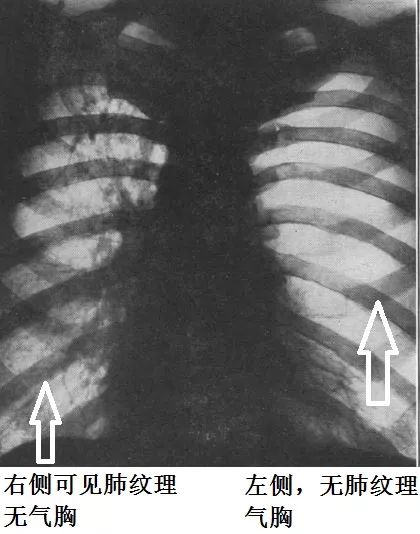

下面怎么办?慢性气胸很可能是非流动性气胸:气胸可能不随着体位大幅度变化。那么,在穿刺之前,做一个站立位胸片就显得很有必要。

后来患者做了站立位胸片,结果显示:选择锁骨中线第二肋间穿刺抽气,是很不妥当的。

气胸主要在左下肺,左上肺的肺纹理清楚可见。

左上肺放大,如下:

很明显,患者的气胸没有往高处走。贫穷限制了我们对奢侈生活的想象力,胸膜的粘连限制了气胸的流动性。

对于这个患者,既然锁骨中线第二肋间不适合胸腔穿刺,那么选择哪个位置呢?

结合CT,选择腋前线第五、六肋间穿刺抽气,更妥当。